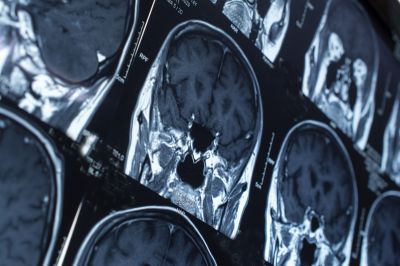

Ученые из Центра исследований инсульта Лондонского университетского колледжа провели метаанализ данных четырех клинических исследований, в которых оценивалось оптимальное время начала приема прямых пероральных антикоагулянтов (ПОАК) после острого ишемического инсульта. Результаты метаанализа CATALYST опубликованы в журнале The Lancet.

Анализ показал, что у пациентов, которые начали прием ПОАК в течение первых четырех дней после инсульта, частота повторных ишемических инсультов в течение 30 дней была ниже — 2,1 против 3%. Риск снижался на 34%. При этом частота симптоматического внутримозгового кровоизлияния не различалась между группами. Авторы также отметили, что раннее назначение ПОАК может способствовать лучшей приверженности лечению и снижению длительности госпитализации.

Анализировали данные 5 441 пациента с острым ишемическим инсультом и фибрилляцией предсердий, включенных в исследования TIMING, ELAN, OPTIMAS и START. У большинства участников диагностировали инсульт легкой или умеренной степени тяжести: средний показатель по шкале NIH составлял 5 баллов, средний возраст — 77,7 года. Среднее время до начала терапии составляло три дня в группе раннего начала ПОАК и 7,2 дня — в группе отложенного. |

Авторы заключили, что раннее назначение ПОАК в течение четырех дней после инсульта у пациентов с фибрилляцией предсердий снижает риск повторных инсультов без повышения риска внутричерепных кровоизлияний. Однако полученные данные относятся преимущественно к пациентам с инсультом легкой или умеренной степени тяжести, поэтому в сложных случаях решение о начале терапии должно приниматься индивидуально.